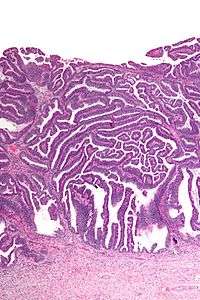

| Micrograph of a villoglandular adenocarcinoma the cervix. H&E stain. | |

The name of the lesion describes it microscopic appearance. It has nipple-like structures with fibrovascular cores (papillae) that are long in relation to their width (villus-like), which are covered with a glandular pseudostratified columnar epithelium.

Very low mag.